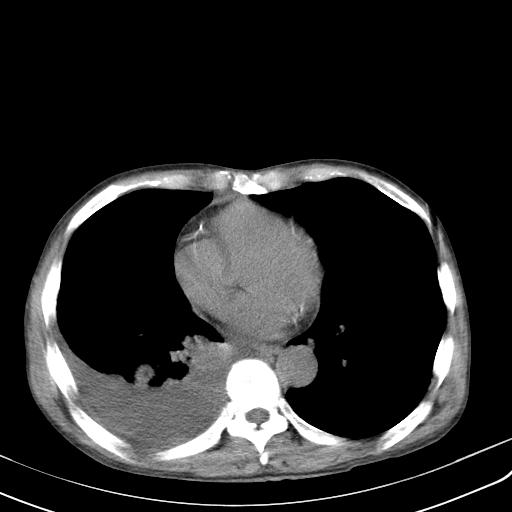

男性 75  咳嗽 一周前发热最高达39

右肺继发型tb并右侧tb性胸腔炎,右侧胸腔大量积液并右下肺膨胀不全,慢支肺气肿、多发肺大泡。建议抽胸水实验室检查并复查排除恶性在占位。

右上肺继发型肺结核,右胸腔中等量积液。

左上肺大泡。

结核的基础上有纵隔淋巴结肿大,右侧有胸水,但右侧纵隔反而窄,说明有肺有不张。

再就是右下肺有块影,和不张混合,还是不能除外肺癌。

补充材料,患者2月份ct片大致正常,双侧胸腔积液,2月份抽胸水未发现ca细胞,现患者发热,痰多,各气管通畅,

1)右肺继发型肺结核。2)左肺胸膜下多发性肺大泡。3)右侧胸腔积液。